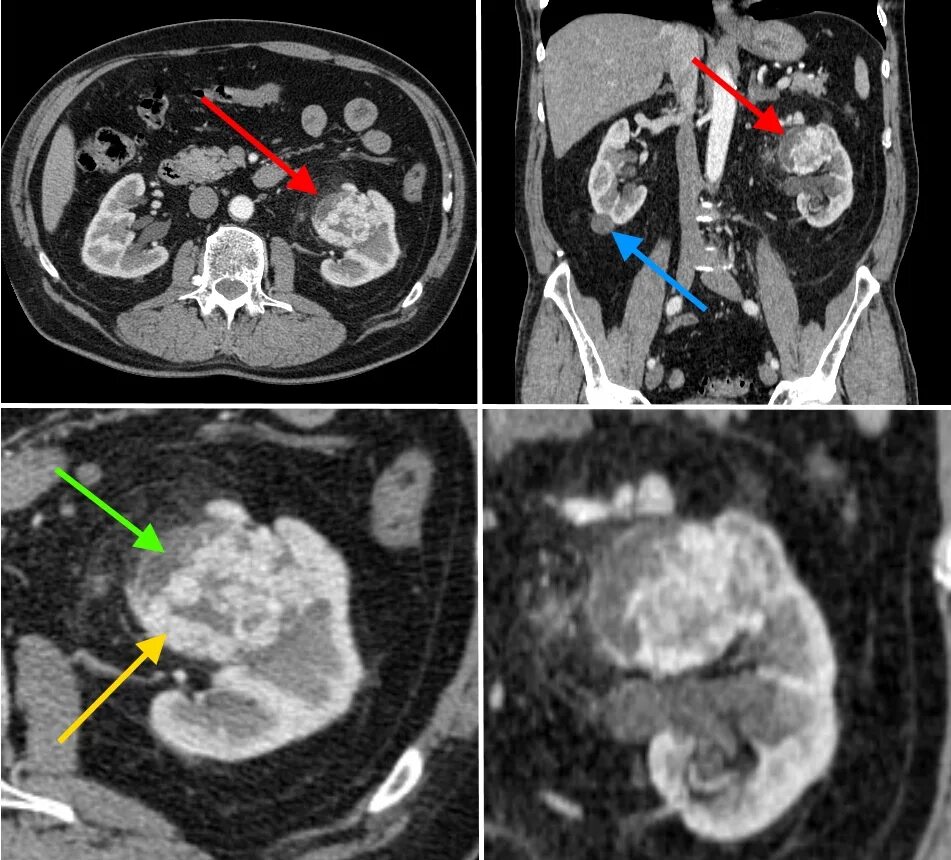

Как выглядит кт с контрастом